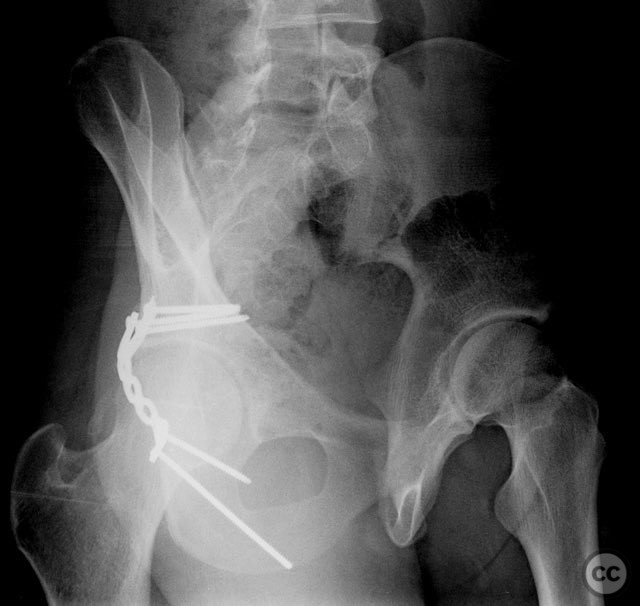

Intraoperatively, the posterior wall fragment was found firmly embedded within the abductor musculature, necessitating careful disimpaction and minimal periosteal stripping to preserve vascularity. The spring-hook device provided secure capture of the peripheral fragment without involving the labrum. Placement of the reconstruction plate medial to the hook tines provided buttress support to prevent secondary displacement. Fluoroscopic imaging confirmed anatomic reduction and extra-articular screw placement. Postoperative CT demonstrated satisfactory reduction and implant positioning.

Postoperative protocol:   Early passive range of motion exercises were initiated postoperatively, avoiding hip flexion beyond 90 degrees and abduction beyond 20 degrees for six weeks. Toe-touch weight bearing was maintained for six weeks, progressing to partial weight bearing at eight weeks, and full weight bearing as tolerated by twelve weeks. Return to athletic activity was permitted at four months post-injury following clinical and radiographic confirmation of healing.

Follow up:   At one year post-injury, radiographs demonstrated maintained reduction and implant integrity. The patient returned to competitive basketball four months after surgery without restriction.

Orthopaedic implants used:   Spring-hook acetabular fixation device; 3.5 mm reconstruction plate; cortical screws (extra-articular).